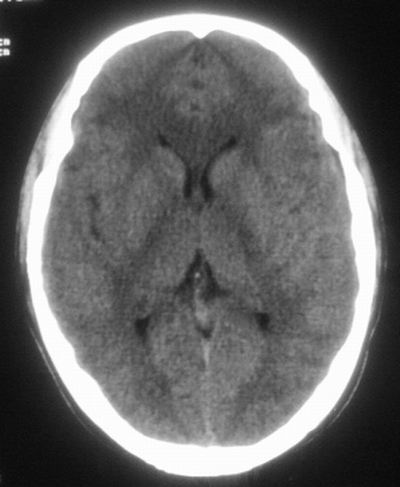

治疗三天后复查ct片示:

治疗三天后复查ct:除左侧额顶叶血肿外。左侧额叶另见片状低密度灶,密度不均匀,境界不清;考虑脑梗塞。